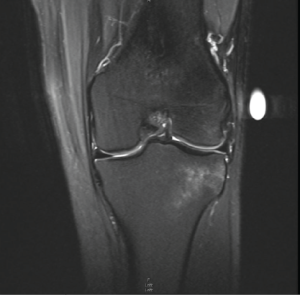

Arthroscopy was done to reconstruct the ACL with quadriceps autograft. The midsubstance ACL tear was apparent. There were no abnormalities appreciated on the cartilaginous surfaces throughout, and there were no disruptions to the body of the plateau. Both the medial and lateral menisci were intact. However, an anatomic variant was discovered at the lateral meniscus. The anterior horn continued superiorly and attached to the torn ACL, which was better appreciated on the MRI during re-review postoperatively (Fig. 2 and 3). Due to the superfluous nature of the variant, the tear did not impact the body of the meniscus in any way. The root of the lateral meniscus remained intact. The redundant tissue was gently debrided away without compromising the root.

Figure 3: Coronal magnetic resonance imaging showing Patient 1’s anterior horn of the lateral meniscus extending into the anterior cruciate ligament footprint.